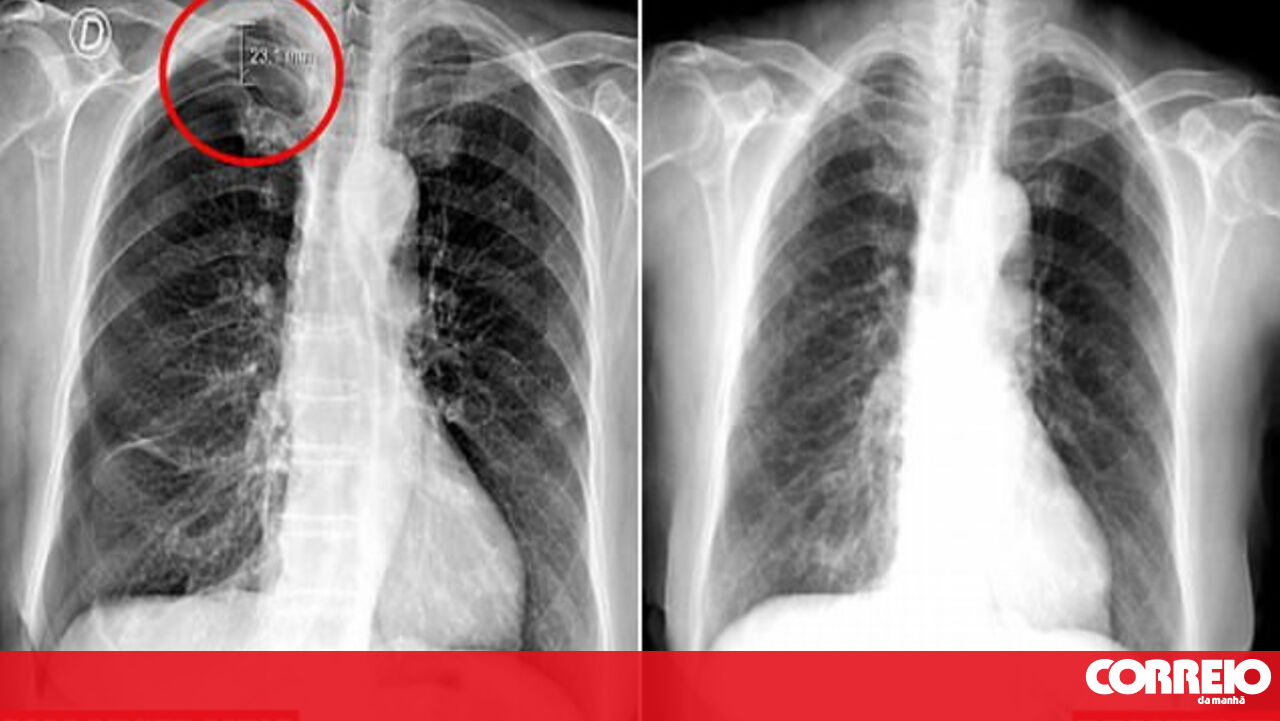

Um tratamento de acupuntura provocou o colapso do pulmão de uma mulher portuguesa de 79 anos, de acordo com os médicos do Centro Hospitalar Universitário da Central de Lisboa.

Os médicos descobriram que parte do pulmão direito teria entrado em colapso e culparam as agulhas usadas na acupuntura.

A senhora teve uma recuperação completa em poucos dias, mas os médicos alertaram que a prática inadequada pode levar a problemas como o risco de vida, segundo jornal britânico Daily Mail.